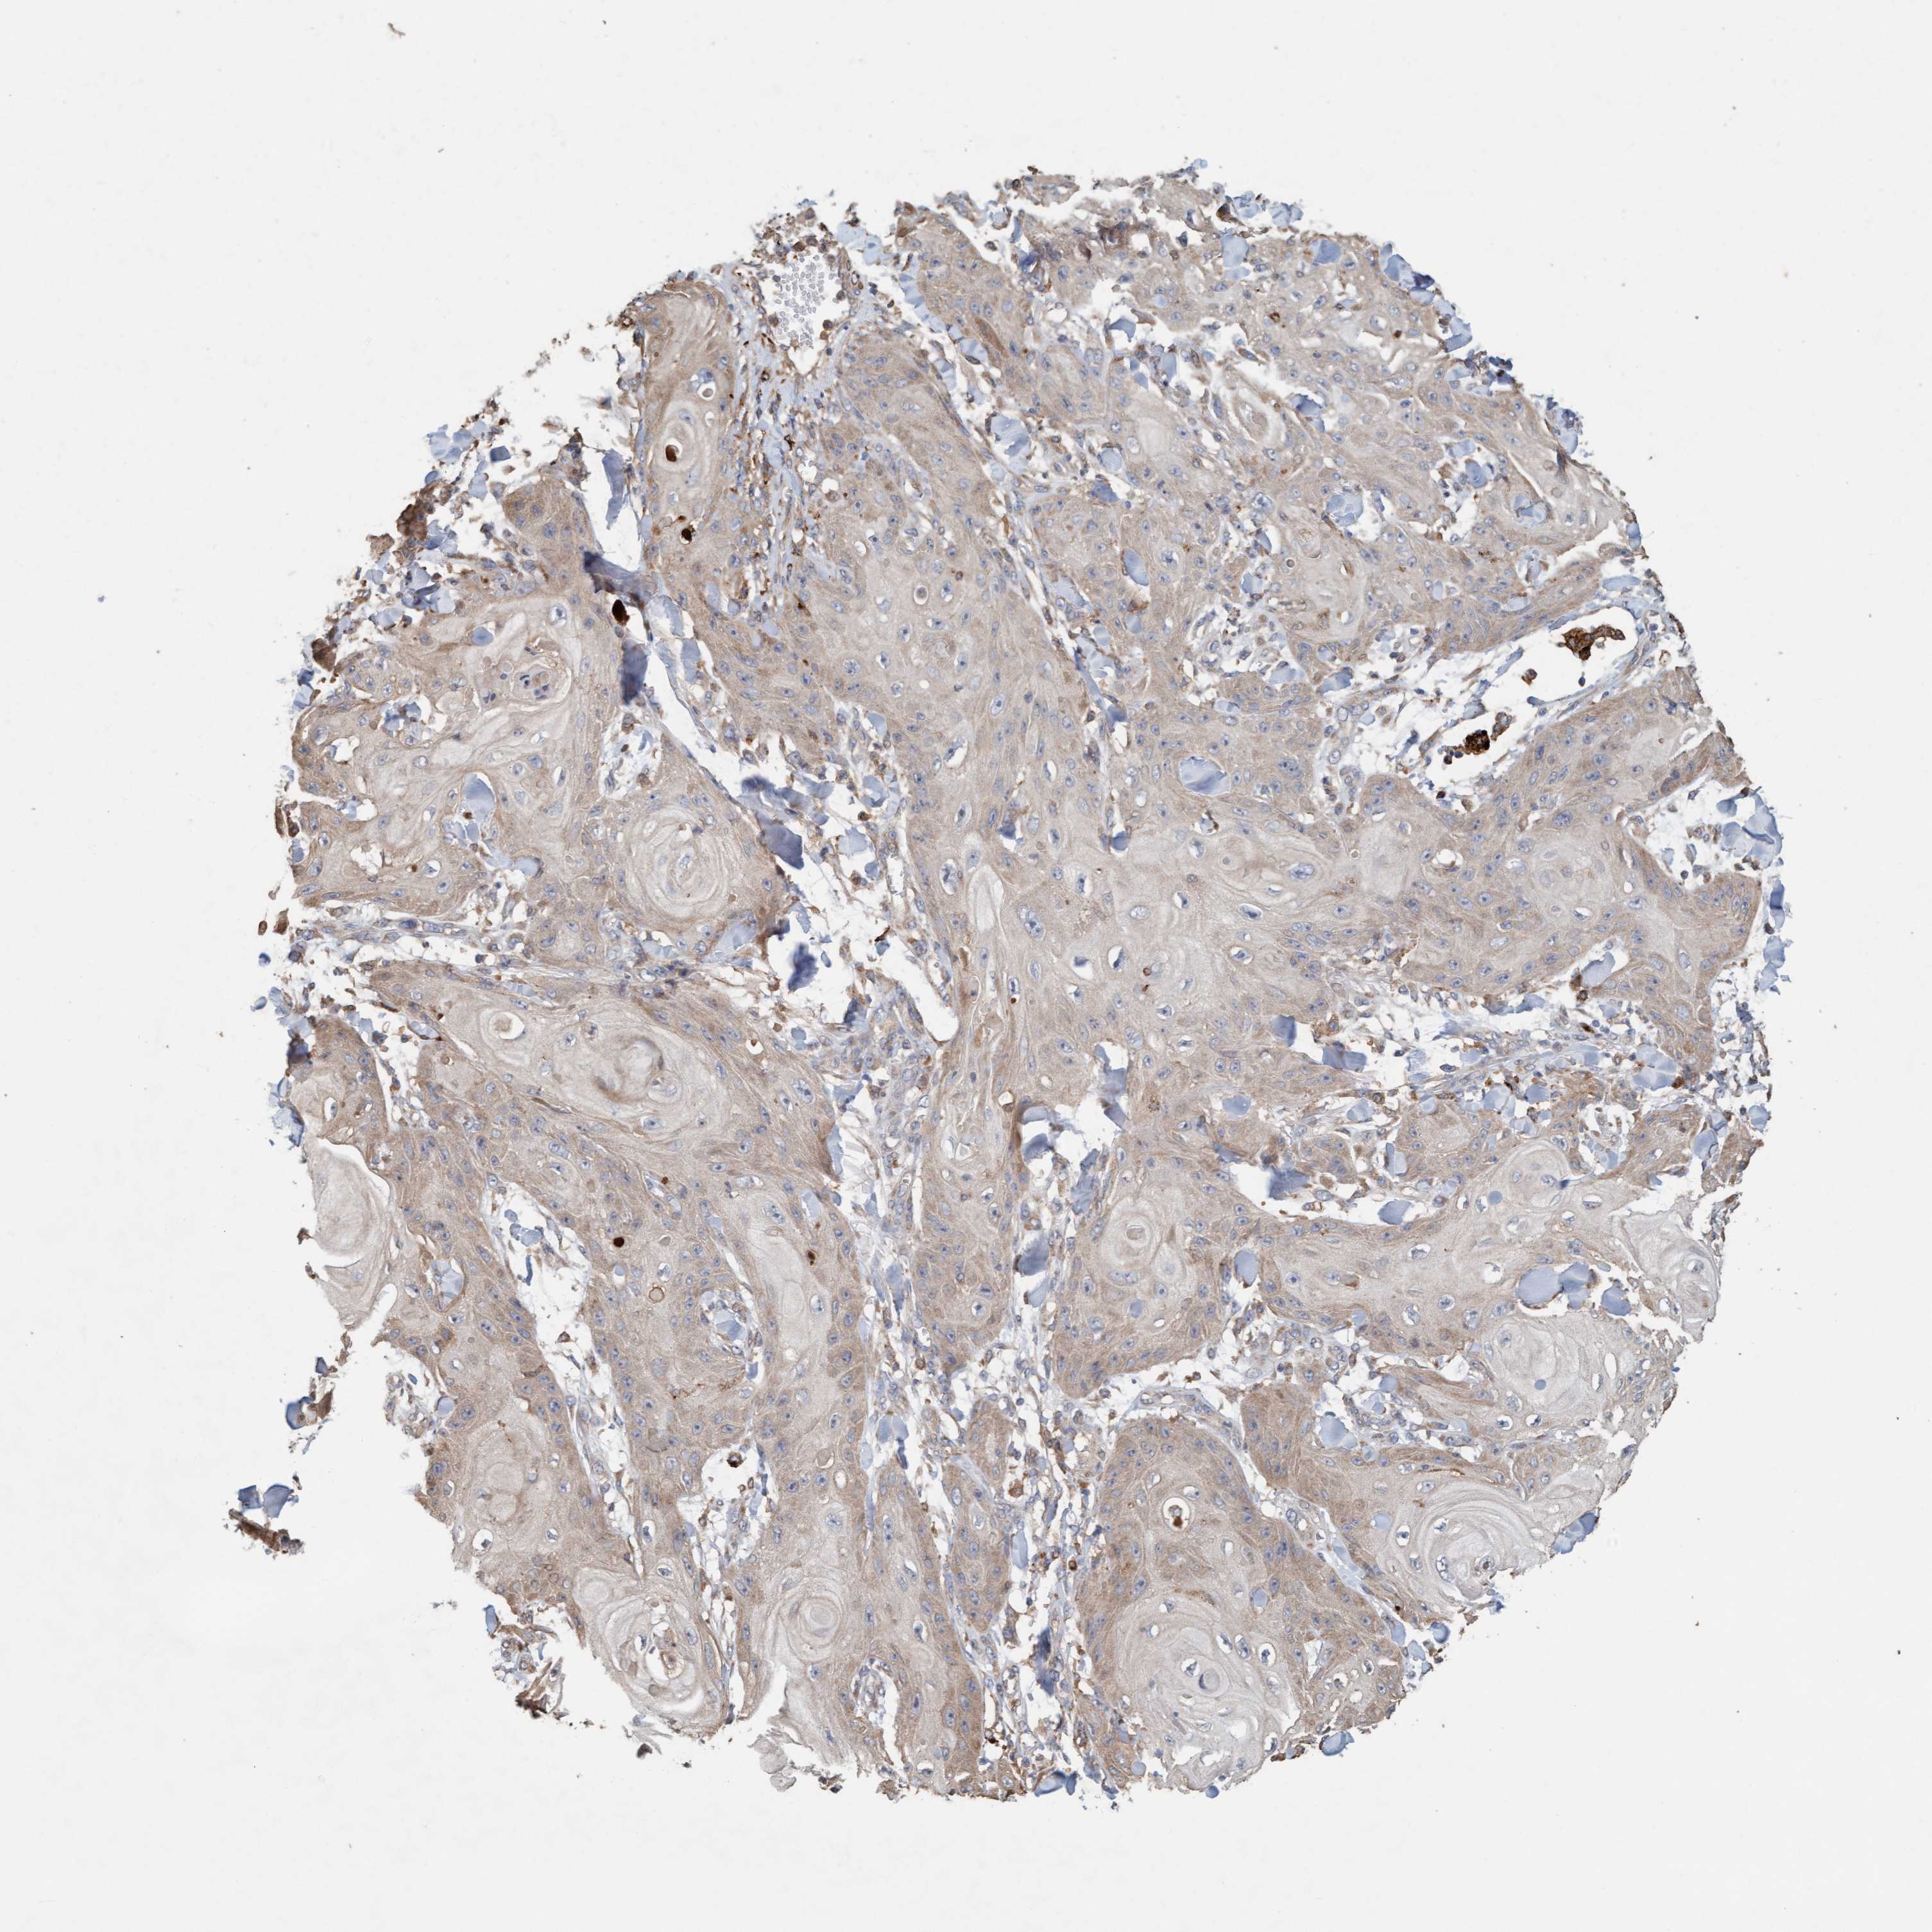

CANCER SKIN CANCER Show tissue menu

Basal cell and squamous cell cancer

SKIN CANCER - Protein expressioni

A mouse-over function shows sample information and annotation data. Click on an image to view it in a full screen mode. Samples can be filtered based on level of antibody staining by selecting one or several of the following categories: high, medium, low and not detected. The assay and annotation is described here.

Each image is clickable and will lead to virtual microscopy that enables deeper exploration of all samples and also displays staining intensity scores, fraction scores and subcellular localization as well as patient and tissue information for each sample.

Antibody HPA023584

Antibody HPA024814

Basal cell carcinoma

Squamous cell carcinoma, NOS

Squamous cell carcinoma, metastatic, NOS